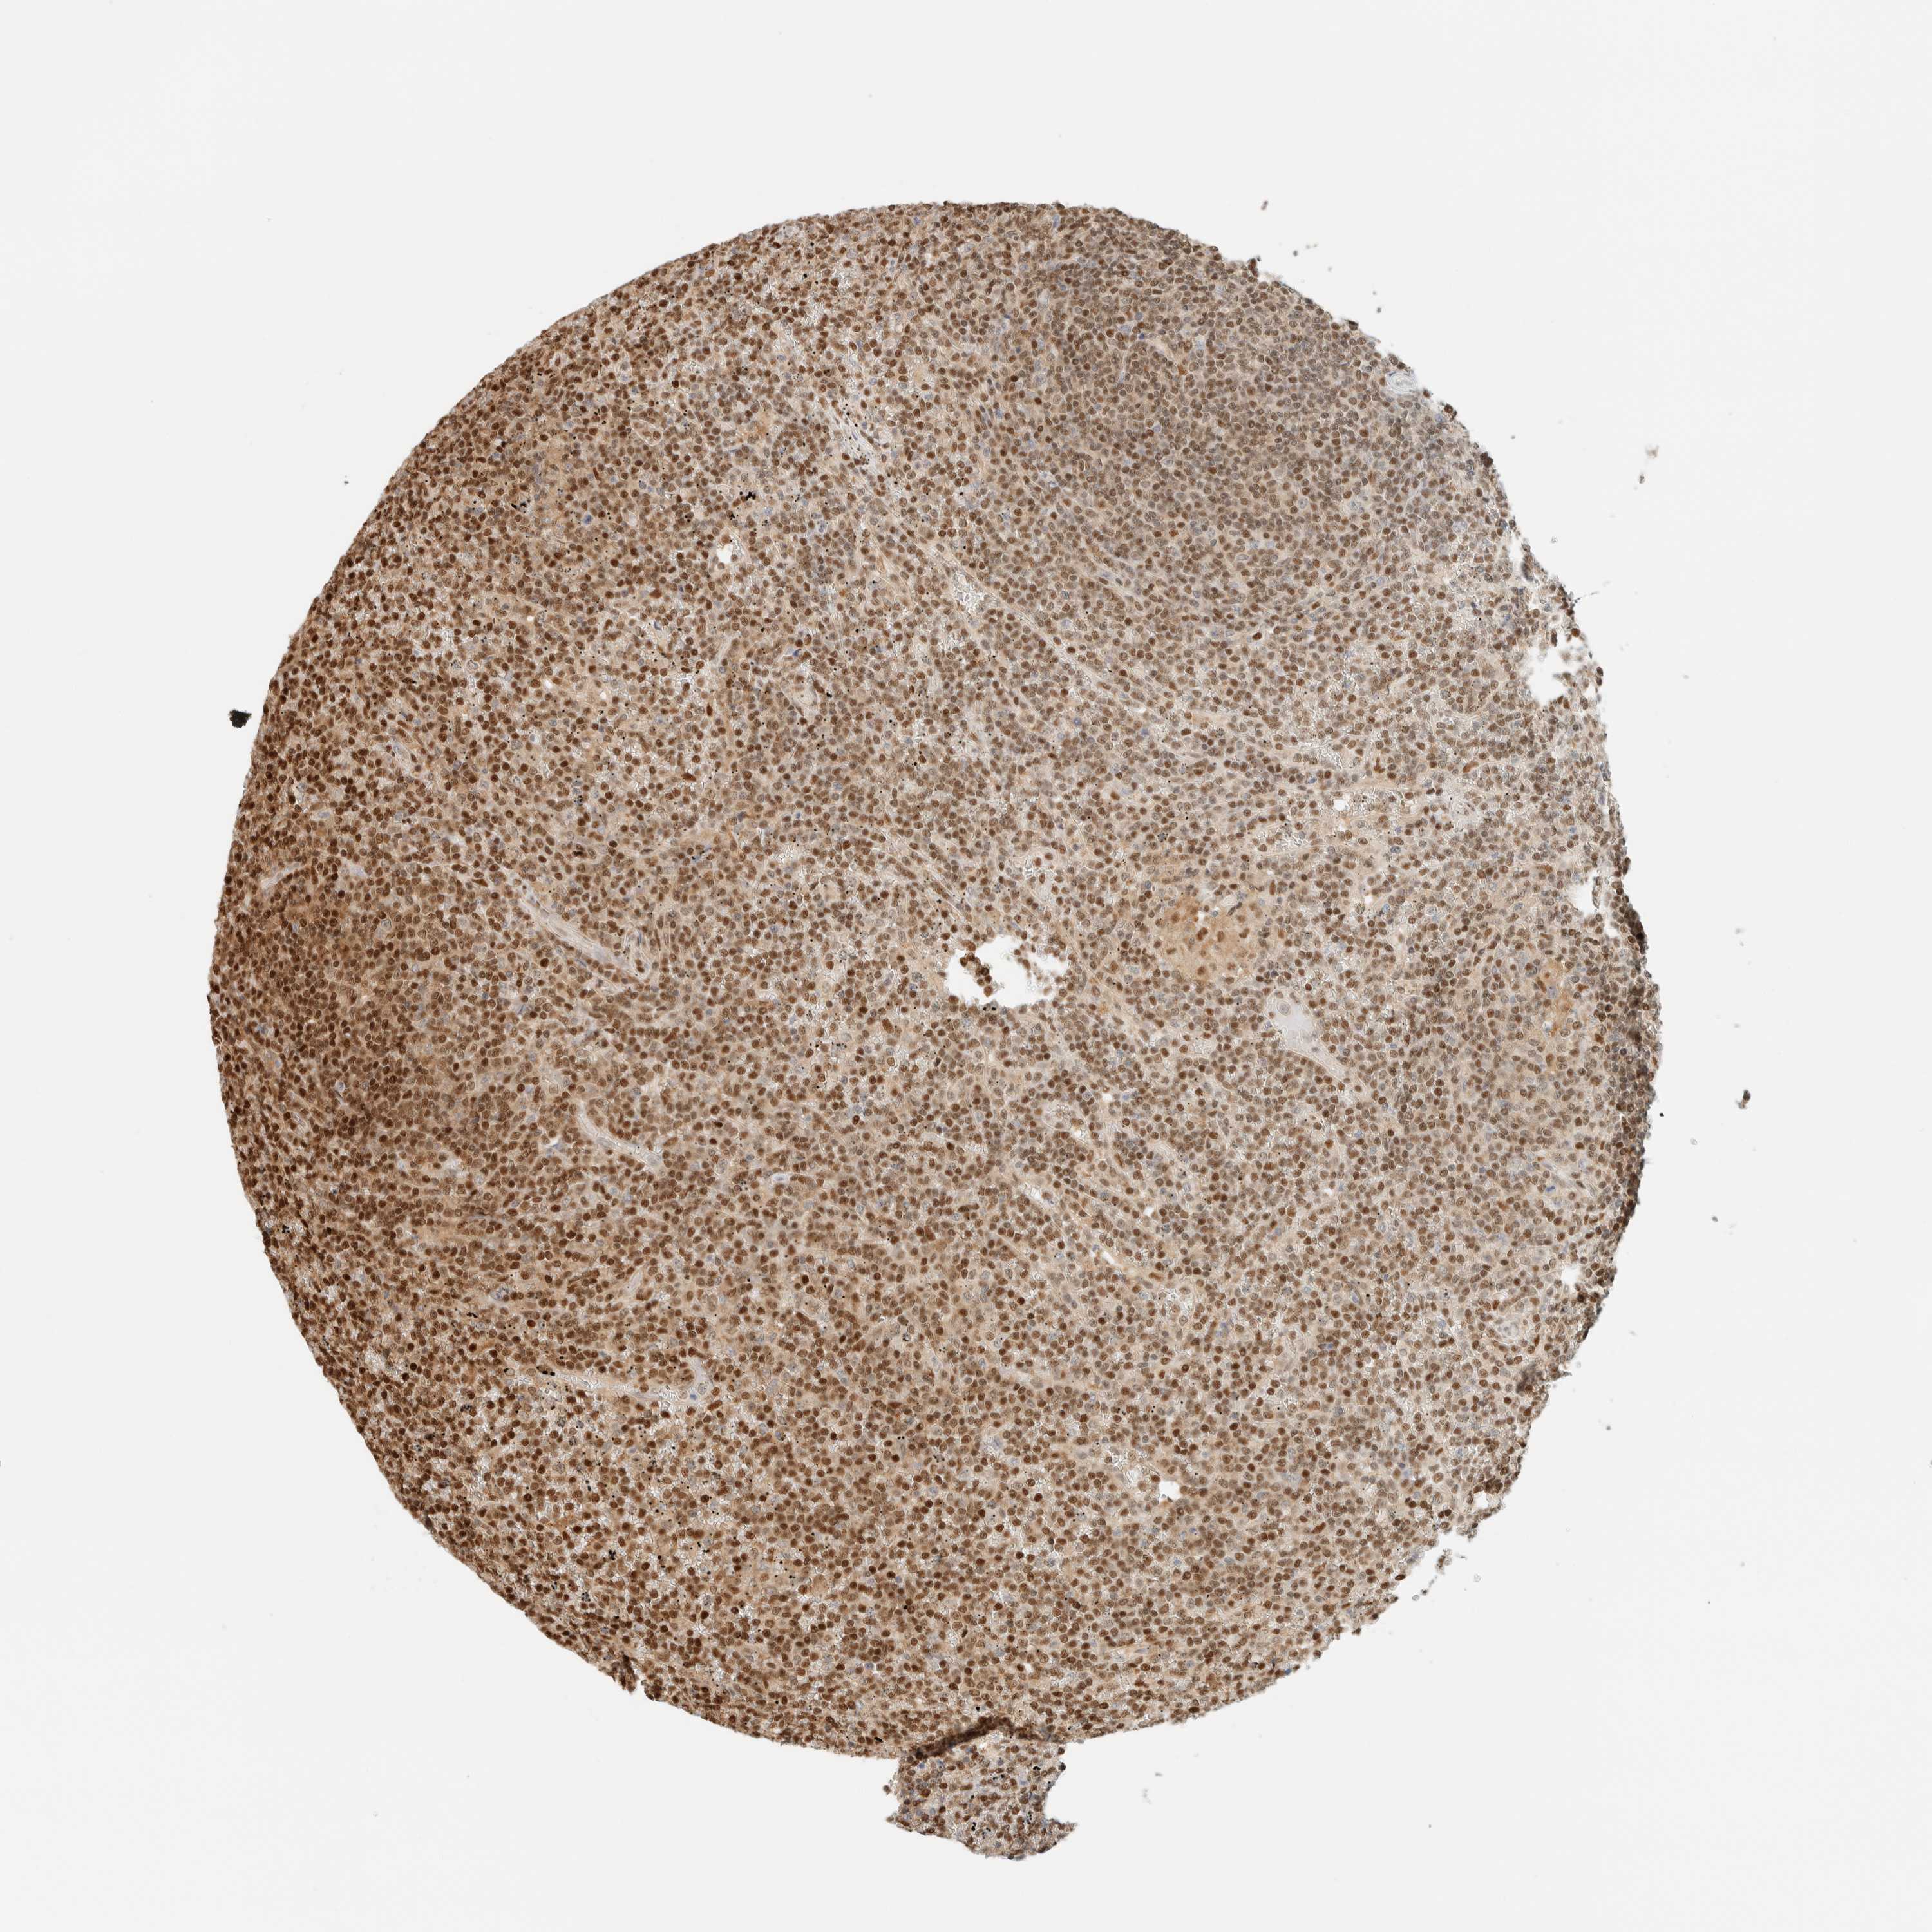

CANCER LYMPHOMA Show tissue menu

LYMPHOMA - Protein expressioni

A mouse-over function shows sample information and annotation data. Click on an image to view it in a full screen mode. Samples can be filtered based on level of antibody staining by selecting one or several of the following categories: high, medium, low and not detected. The assay and annotation is described here.

Each image is clickable and will lead to virtual microscopy that enables deeper exploration of all samples and also displays staining intensity scores, fraction scores and subcellular localization as well as patient and tissue information for each sample.

Antibody HPA023438

Staining

High

Intensity

Strong

Quantity

>75%

Location

Nuclear

Hodgkin's disease, NOS

Malignant lymphoma, non-Hodgkin's type, High grade

Malignant lymphoma, non-Hodgkin's type, Low grade